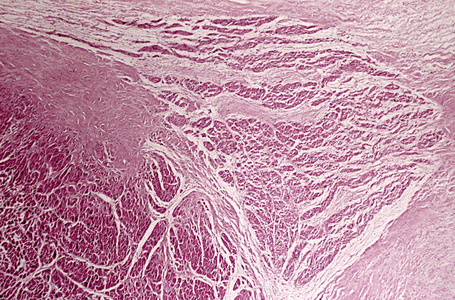

图像名称窦房结低倍镜

房室结房室结的高倍镜观察照片

图片尺寸455x300